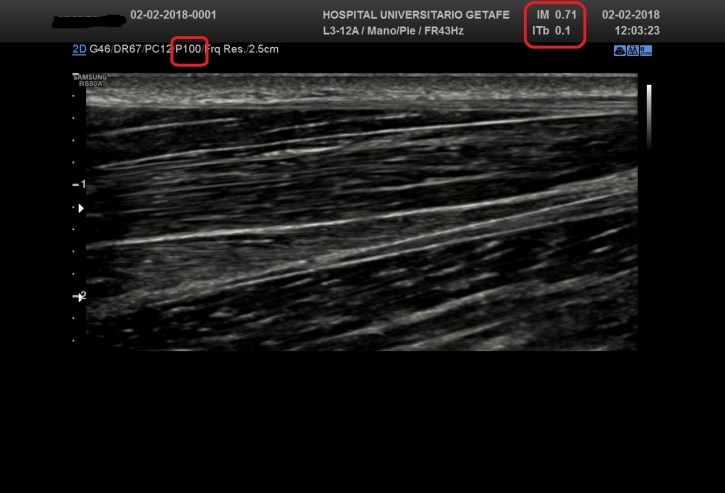

Ambos valores pueden estar representados en la imagen y deben seguir estas normas:

– Deben ser claramente visibles en pantalla cuando el valor sobrepase un 0,4.

Las imágenes a continuación expuestas nos enseñan como la Potencia influye decisivamente en la calidad de la imagen obtenida y además como los IM e IT se ven afectados según el valor de dicha potencia…observa.

If we decrease this percentage, we lower the value of the aforementioned indexes and also the image quality, so beware … The following images show us how the Power decisively influences the quality of the image obtained and also how the IM and IT are affected according to the value of said power … observe.